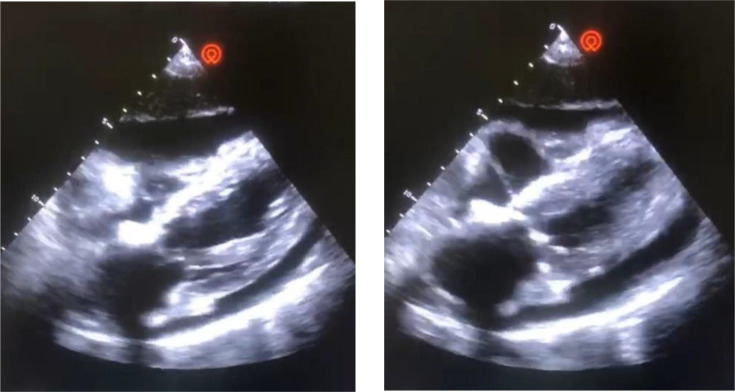

Tuberculosis remains a major public health issue in Morocco. Pulmonary tuberculosis is the most common form, but various extrapulmonary forms exist. Tuberculous pericarditis is a rare form of extrapulmonary tuberculosis that can be complicated by cardiac tamponade, pericardial constriction or their combination, which can threaten the patient's life. Its clinical and radiological signs are nonspecific, and the clinical presentation can be misleading and incomplete, sometimes even with an initial tamponade. We report the case of a 68-year-old female patient admitted for intense retrosternal chest pain associated with acute dyspnoea, evolving in the context of unquantified weight loss and general deterioration. Additionally, she reported a history of fever and night sweats. Clinical examination revealed a conscious, febrile, hypotensive, tachycardic, polypneic patient with good oxygen saturation, signs of right heart failure and muffled heart sounds on auscultation. Chest X-ray revealed cardiomegaly, and the ECG showed diffuse low voltage. Given the presence of Beck's triad suggestive of cardiac tamponade, a transthoracic echocardiogram was performed, revealing a large pericardial effusion with a 'swinging heart'. A chest CT scan also confirmed the large pericardial effusion. The diagnosis of cardiac tamponade was made based on the clinical and radiological findings, and pericardial drainage was performed, after which the patient showed clinical improvement. PCR GenXpert MTB/RIF Ultra detected the presence of Mycobacterium tuberculosis in the pericardial fluid, with no resistance to rifampicin. Culture was positive for M. tuberculosis. The diagnosis of tuberculous pericarditis was, thus, confirmed, and the patient was started on quadruple antituberculosis therapy with good clinical progress.